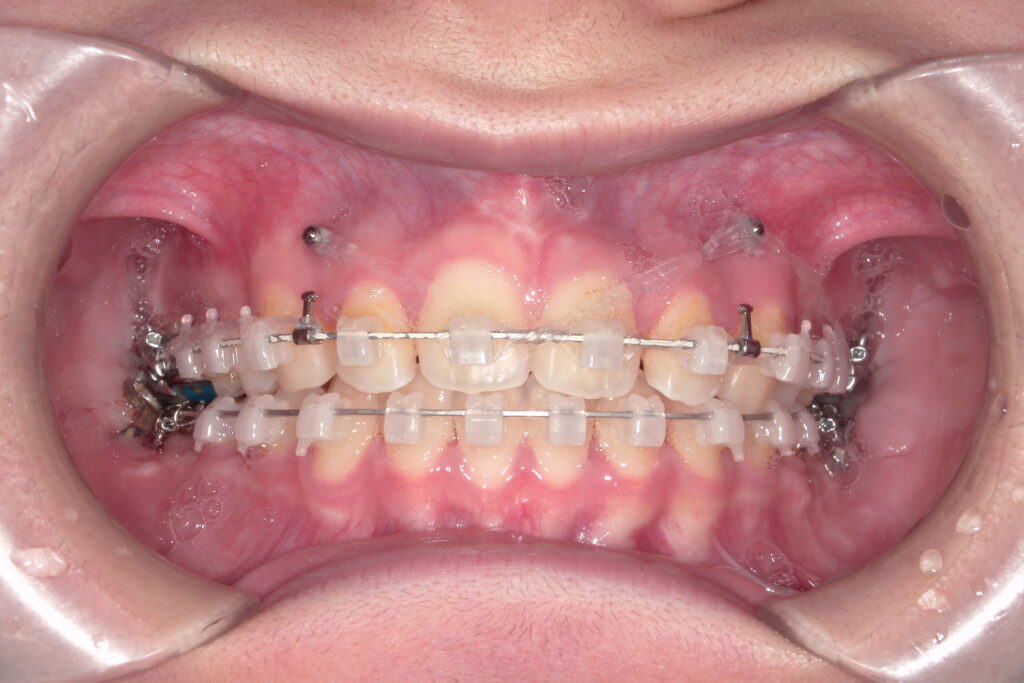

表側矯正は、歯の表面にブラケットと呼ばれる小さな装置を装着し、それにワイヤーを通して歯を少しずつ動かしていく治療方法です。もっとも古くから使われているスタンダードな方法で、幅広い症例に対応できるのが大きな魅力です。最近では、アンカースクリュー(ネジ)を併用することで、従来の治療よりも出っ歯や過蓋咬合(深い咬み合わせ)の治療が効率的に進められるようになりました。当院では、歯の色になじみやすいオールセラミックブラケットや、白くコーティングされたホワイトワイヤーも選択可能で、目立ちにくさにも配慮しています。

- 幅広い不正咬合に対応可能(出っ歯・受け口・開咬・叢生など)

- 比較的費用が抑えられる

- 装置の安定性が高く、効率的に動かせる

- 金属アレルギーでも使用できる(クリアティウルトラのみ)

装置が見えるため、審美的にはやや劣る

歯磨きがしづらく、虫歯のリスクがやや高まる

装着直後は痛みや違和感を感じることがある